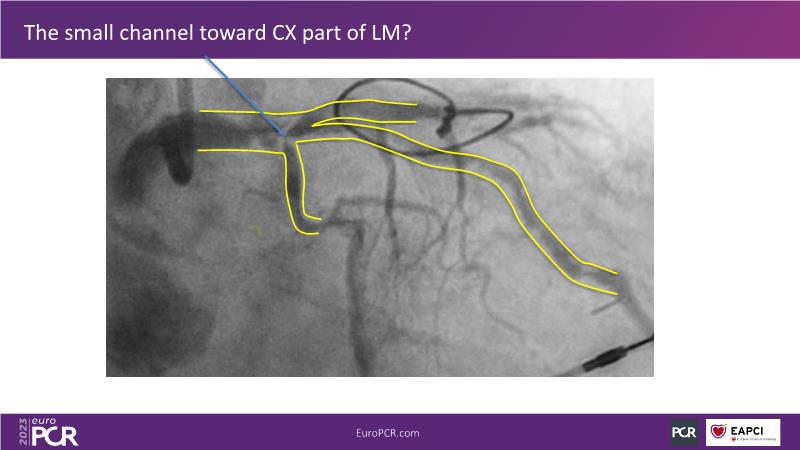

The aim of this session is to address the question of how to optimise outcomes for high-risk patients by analyzing two real-life cases for discussion: a distal calcified left main trifurcation and a high-risk PCI with orbital atherectomy.

- To learn how the distinct attributes of orbital atherectomy (OA) may help you address challenges in heavily calcified vessels